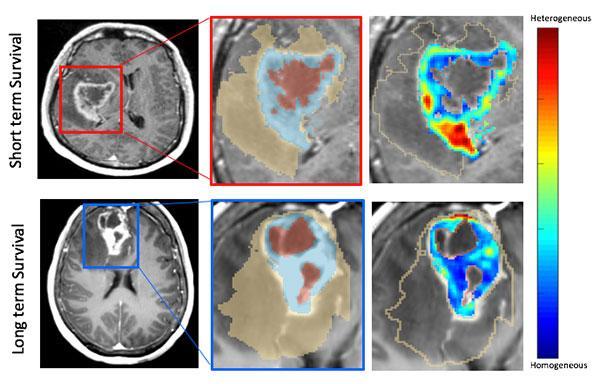

An example of the MRI scans showing long-term and short-term survival indications. Image courtesy of Case Western Reserve University

The AI model used by the researchers leveraged features from the region adjacent to the tumor, as well as inside the tumor to identify which patients had a poor prognosis, Pallavi said. Then, they used gene-expression information to shed light on which biological pathways were associated with those images.

"We can tell you who is at a better risk of survival," Beig said. "What clinicians want to do is give their patient an idea of quality of life, and since roughly 10% of these patients go on to live more than three years, that's important information."